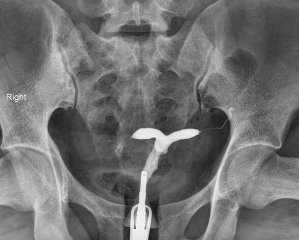

32세 여성이 난임으로 내원하였다. 과거에 세 번의 자연유산이 있었다. 남편의 정액 검사 결과는 정상이었다. 골반 MRI 및 자궁나팔관조영 검사 결과이다. 치료는?

• MRI상 자궁은 부피가 크고 앞쪽으로 기울어져 있으며, 두 개의 자궁강이 septum(low signal density로 보이고 있음)로 나뉘어 있다. 이 저신호는 자궁경부까지 뻗어 있으며, fundus의 평평한 윤곽이 관찰된다. 이는 완전 중격자궁(complete septate uterus)을 시사한다. 쌍각자궁의 경우 fundus에서 1cm 이상으로 깊게 함입되어 있다.